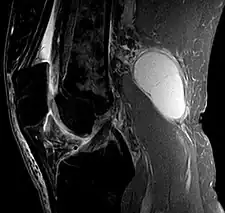

Baker's cyst on MRI, sagittal image